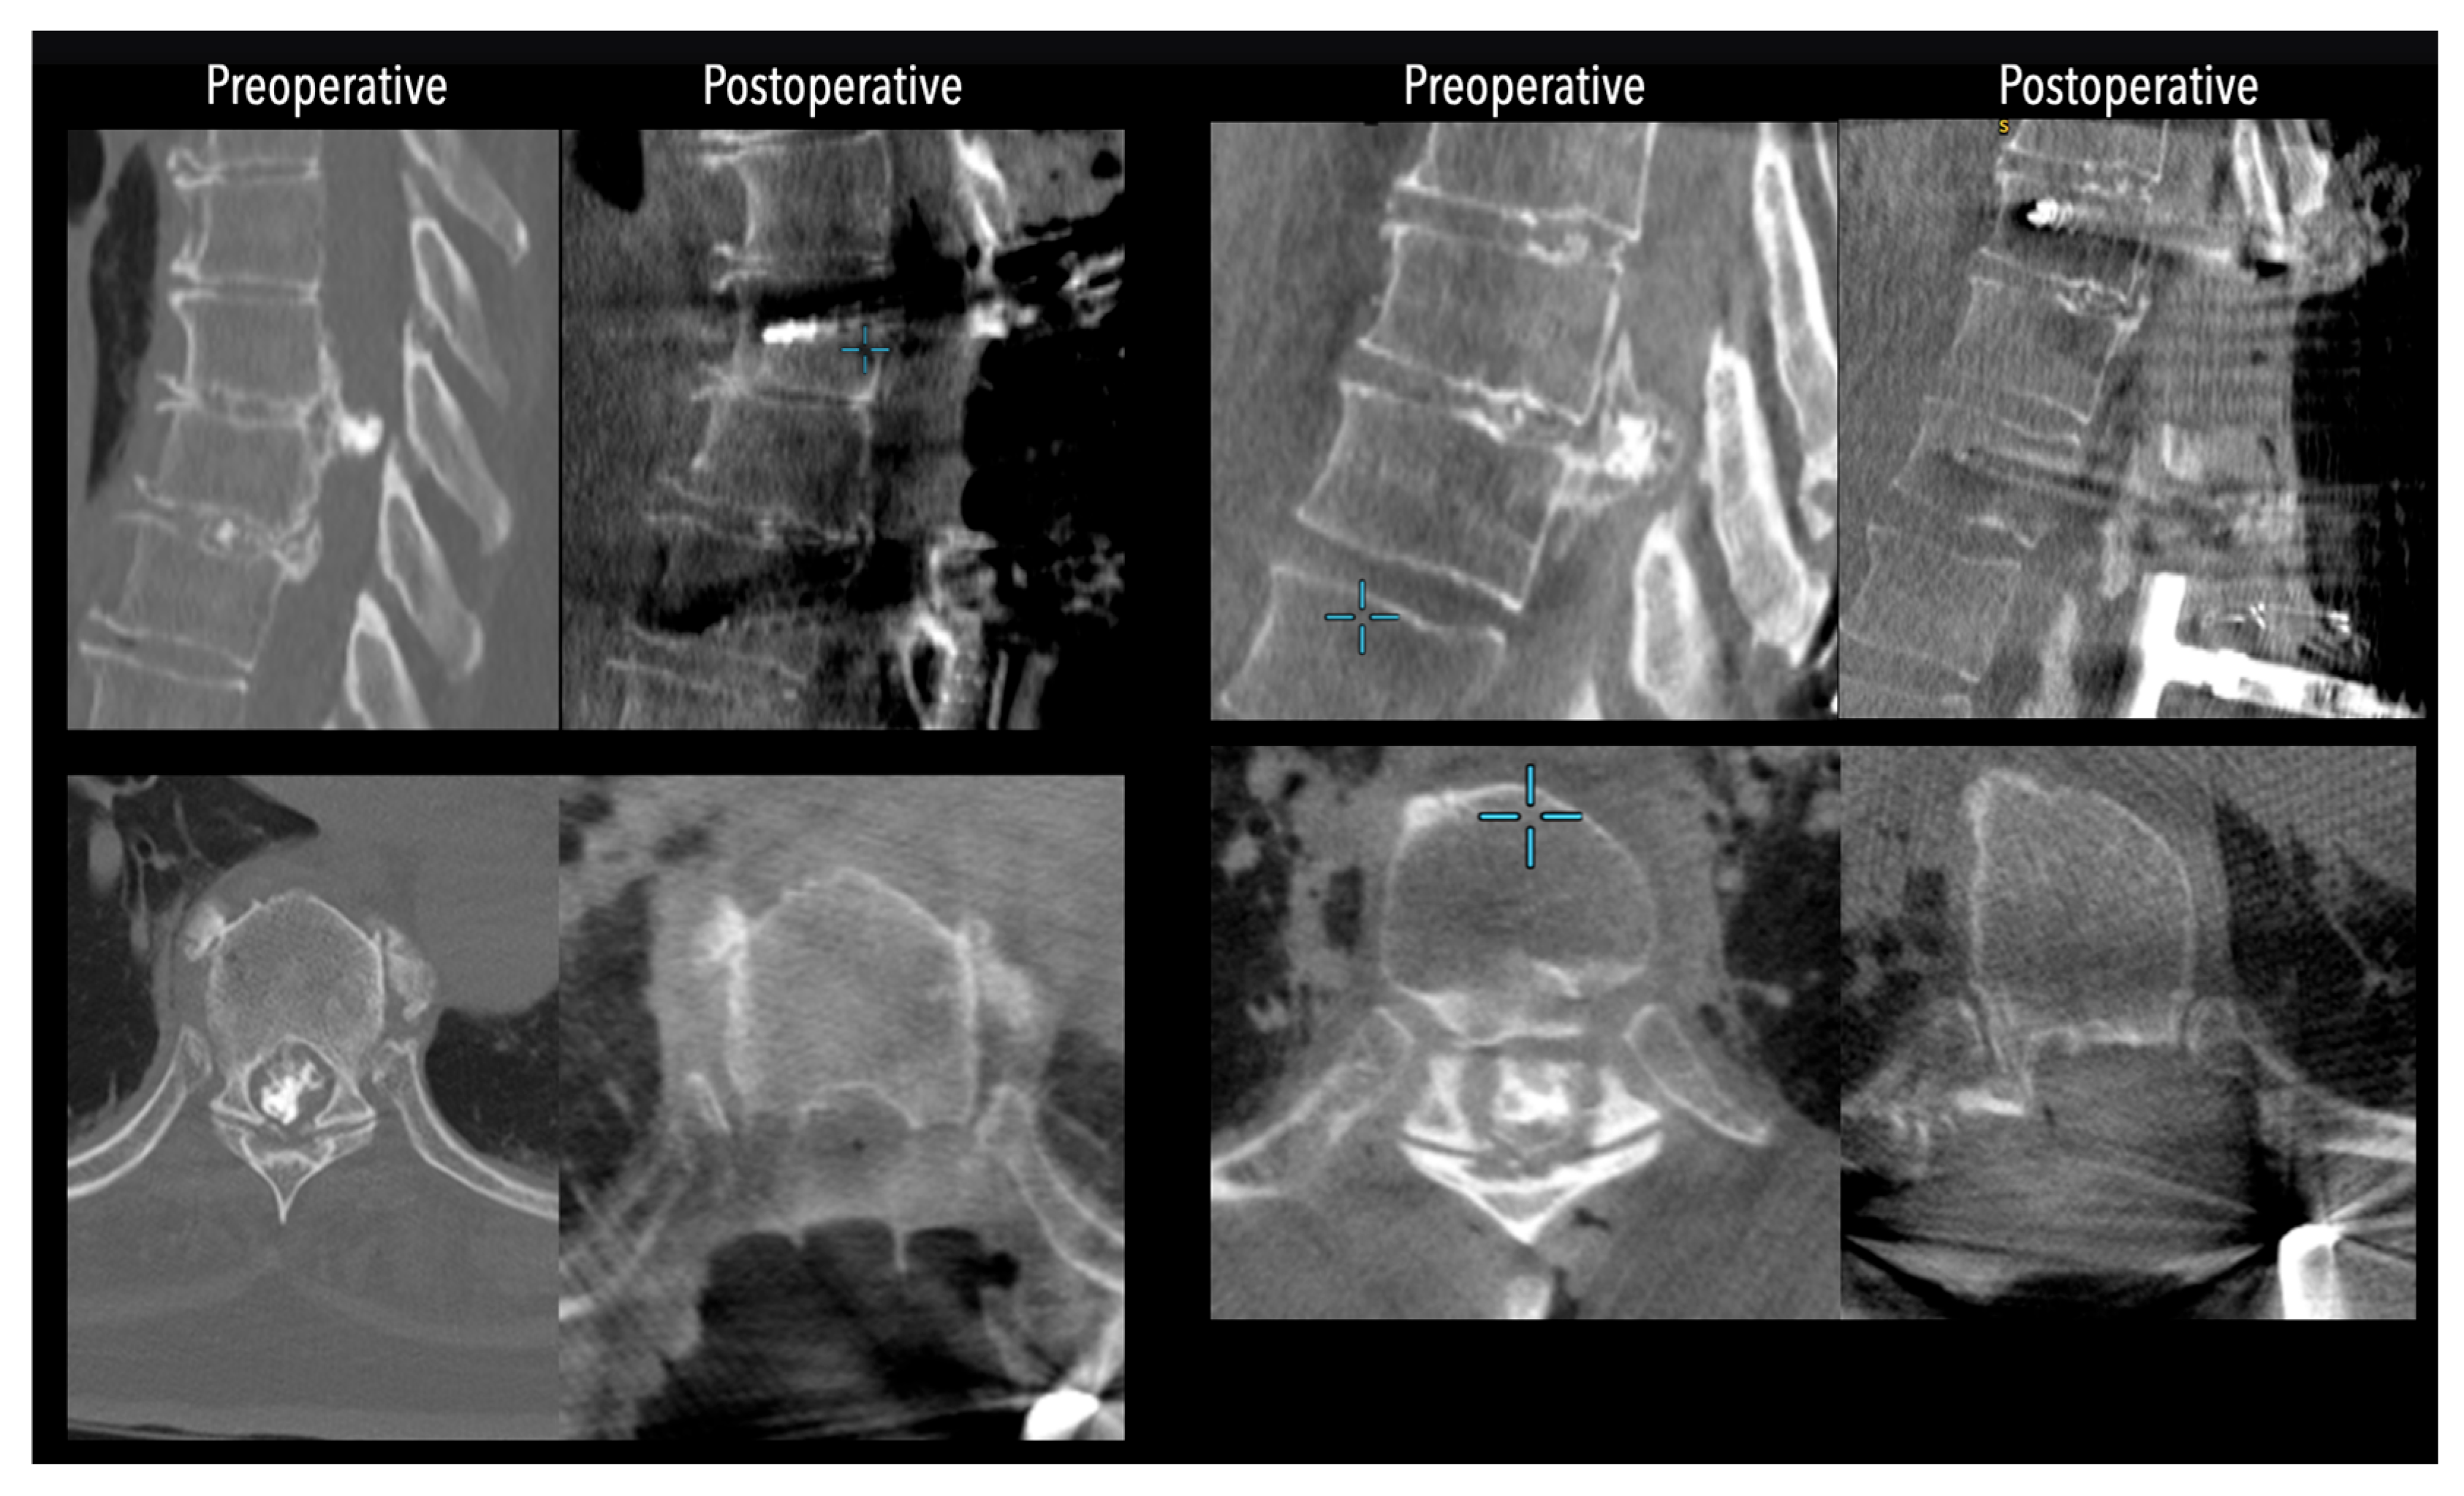

Figure 4. Comparative pre- and postoperative CT scans for two different patients (left and right), illustrating complete discectomy.

Figure 5. Left side: Comparative pre- and postoperative CT scan of a patient, illustrating complete discectomy. Right side: Postoperative X-rays illustrating fixation.

Figure 6. Left side: Comparative pre- and postoperative CT scan of a patient (axial views), illustrating complete discectomy.

In three of the seven cases, the exiting nerve root at the level of the herniation was ligated due to poor visualization and transected extradurally to improve access. In the remaining four patients, the nerve root was either preserved or dissected intradurally using isocool bipolar diathermy and microsurgical scissors. With gentle medial retraction of the cord under gravity and protection using a micro-patty, the calcified disc was exposed. The ventral dura, when intact, was incised sharply and dissected from the disc surface where possible (Figure 2a,b and Figure 3). Disc removal was performed using a hockey-stick-shaped Misonix bone scalpel with constant irrigation, guided by intraoperative neuronavigation. The disc material was resected to a depth of 1–2 mm beyond the posterior vertebral wall to ensure adequate decompression. A second O-Arm spin was routinely performed following discectomy to confirm satisfactory decompression, especially given the limitations of the postoperative MRI due to the metal artefact (Figure 4, Figure 5 and Figure 6).